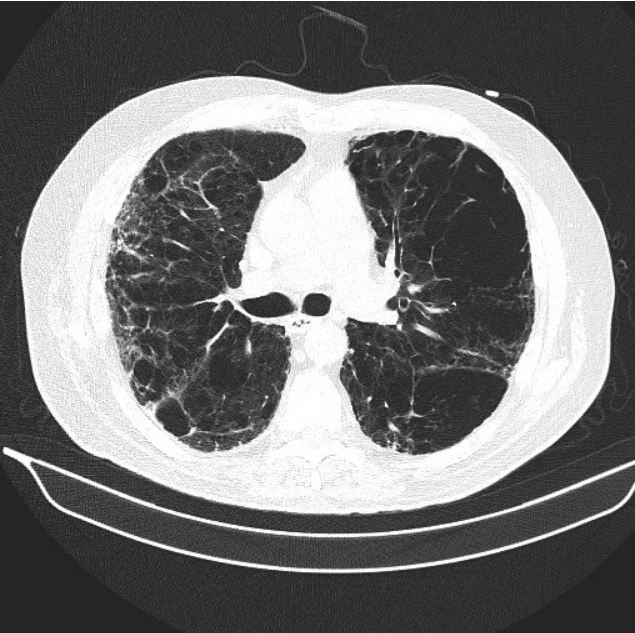

Figure 2.

The primary care physician was concerned about the possibility of interstitial lung disease or pulmonary malignancy. He sent the patient for a high resolution CT of the chest (Figures 1-3; please click figures to enlarge) as well as pulmonary function testing (Table, see next page).